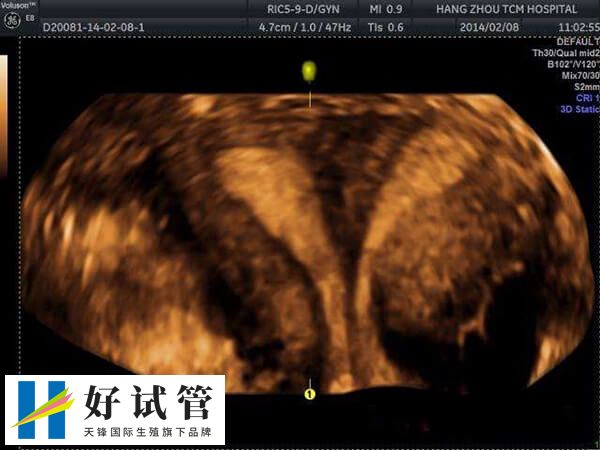

试管婴儿移植是指通过体外受精技术,在实验室中培养出受孕卵子后将其转移到女性子宫内,以实现人工受孕和生育的过程。一般移植胚胎有单个胚胎移植,或是多个胚胎移植,其区别有以下几点: